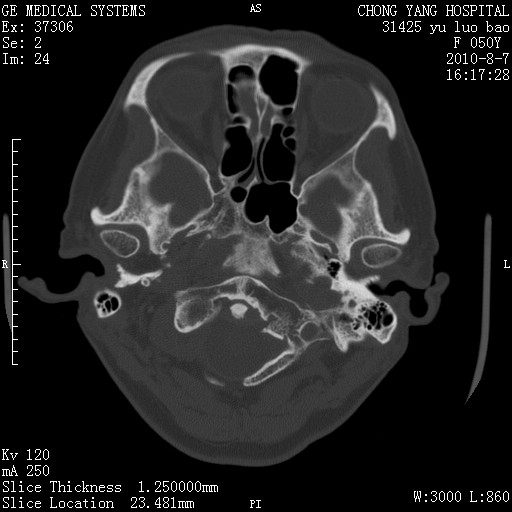

右侧桥小脑角去等密度占位,右侧内听道扩大、骨质吸收,考虑:右侧听神经瘤,建议增强检查。

右侧内听道扩大、骨质吸收,中脑受压左移,考虑:右侧听神经瘤,建议增强检查。支持!

骨窗示右侧内听道扩大,考虑右侧听神经瘤。

右侧桥小脑角区等密度占位,内耳道扩大,听神经瘤